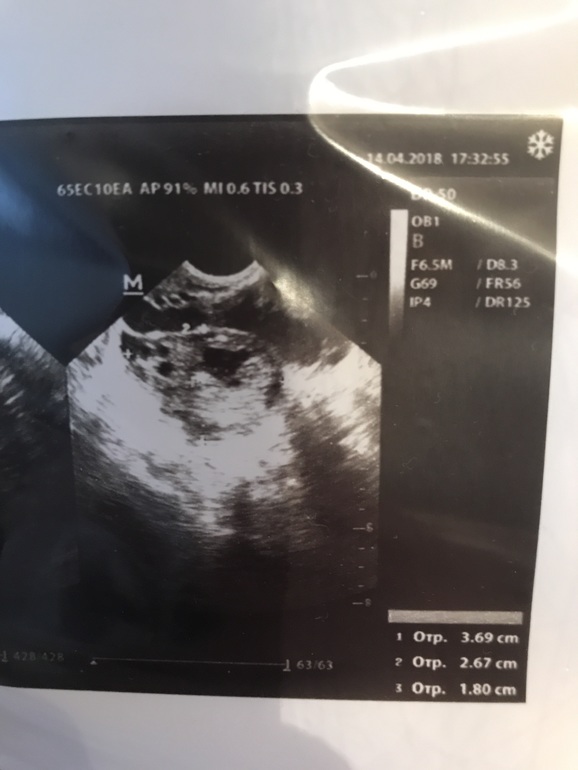

По УЗИ жт с кистой 18мм и эндометрий 22 мм

Киста желтого тела может быть причиной задержки? Или это не киста? (Читала, что до 30 мм не считается кистой). У кого-нибудь было подобное? Пришли месячные или была беременность?